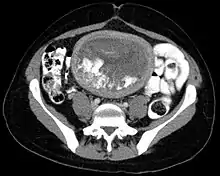

- Hydatidiform mole on CT, axial view